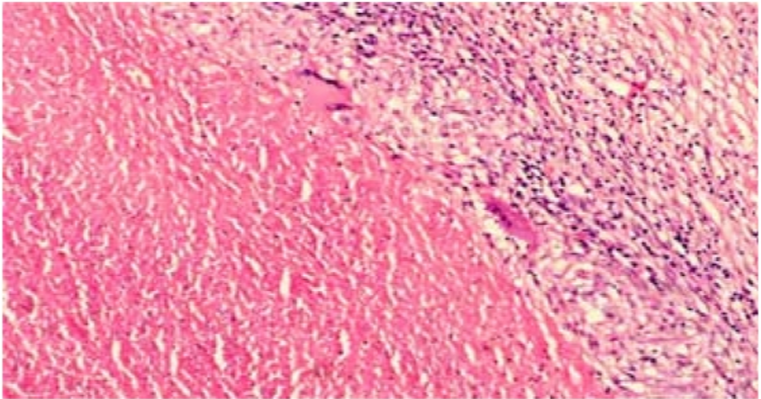

M. tuberculosis in Lymph Node Biopsy Paraffin-Embedded Sections

Our study at Jimma University Specialized Hospital confirmed a high prevalence (61.7%) of tuberculosis lymphadenitis in lymph node biopsies, with a significantly higher occurrence in female patients, necessitating enhanced control and prevention efforts.

Lymph node biopsy showing epitheloid cell changes in H/E stain by 400x. Fragmented or beaded rods (AFB) seen inside and outside macrophages in ZN staining by 400x. Lymphnode biopsy showing giant cells and caseation in H/E stain by 400x.